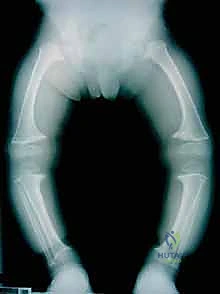

2. الركبة الفحجاء (Genu Varum - Bowlegs)

تُعرف شعبياً بـ "تقوس الساقين". في هذه الحالة، تتباعد ركبتا الطفل عن بعضهما البعض بشكل كبير حتى عندما يكون كاحلاه متلامسين.

شكل 2 • ب. يظهر هذا الصبي البالغ من العمر سنتين، والذي يعاني من خلل التنسج في المشاش، فجوة متزايدة بين لقمتي الفخذ واندفاعاً جانبياً أثناء المشي، مما يتطلب تقييماً طبياً متخصصاً.